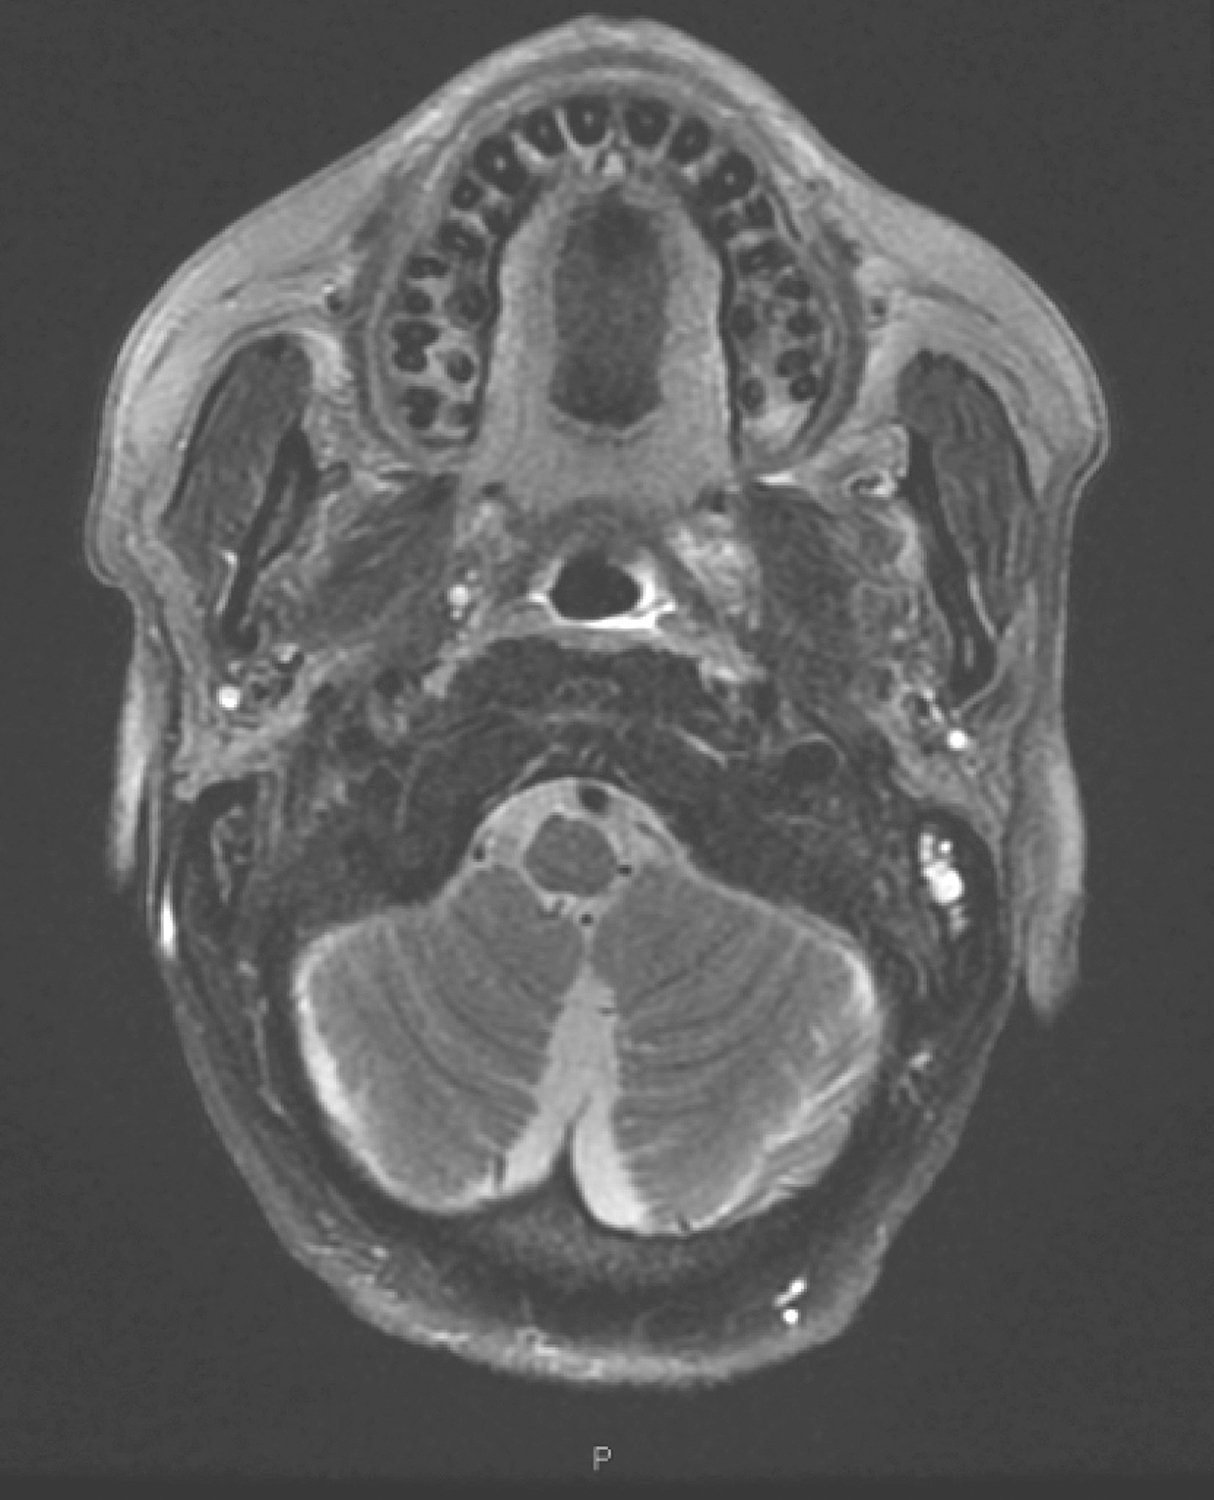

1.2017年3月16日口腔MRI检查

“口咽癌同步放化疗中”复查,与2017年1月12日MR图像比较:

(1)口咽左侧壁肿物现已显示不清,局部仅见口咽壁略增厚,T2WI/FS呈稍高信号,增强扫描中等强化,左侧咽旁间隙仍较模糊,并可见轻度强化(图10),上述请结合镜检并继续随诊。

图10口腔MRI示口咽左侧壁肿物现已显示不清,局部仅见口咽壁略增厚

(2)双侧颌下、颈深多发淋巴结,大者短径约0.5cm,请继续随诊。

4.2017年9月20日颈、口腔、口咽MR

与2017年3月16日MRI比较:

(1)左侧口咽壁略增厚,左侧咽旁间隙略模糊,未见具体肿物,考虑治疗后改变,同前相仿。

(2)双侧颌下、颈深多发淋巴结,大者短径约0.5cm,同前相仿,请继续随诊。